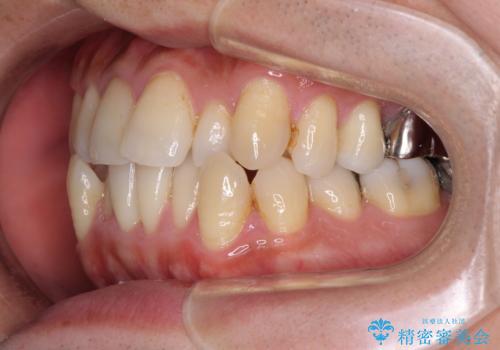

受け口傾向の咬み合わせ 前歯のデコボコをワイヤー矯正で素早く改善

- 前歯の見た目を気にして来院された患者様です。

ワイヤー矯正でもマウスピース矯正でも対応可能とお伝えし、非常に悩まれていましたが、2年後に転勤の可能性が高いとのことで、治療終了までの期間を想定しやすいワイヤー矯正にて治療を行うこととしました。

前歯のクロスバイトは、改善の途中で歯髄壊死を起こすリスクが高くなるため、マウスピース矯正よりもワイヤー矯正をお勧めしております。

この患者様もクロスバイトはあっという間に改善され、1年強で速やかに治療を終えることができました。